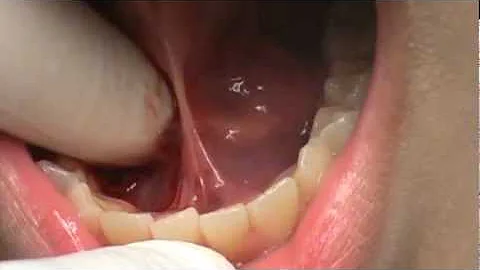

How tongue tie laser surgery for infants and babies works. Minimal invasive, no stitches, no hospital visit and short procedure time ...